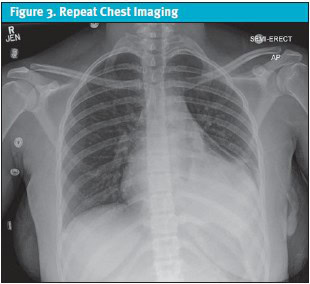

Given the serological findings and the clinical picture of polyserositis (pericarditis and pleuritis), the patient was diagnosed with new-onset SLE. She was started on high-dose corticosteroids (methylprednisolone 30 mg/kg/day for 3 days) and transitioned to scheduled non-steroidal anti-inflammatory drugs (NSAIDs) for pain control. She showed rapid clinical improvement. The pericardial drain was removed on day 2, and the chest tube on day 3, following resolution of effusions confirmed on repeat echocardiogram and chest imaging (Figure 3).